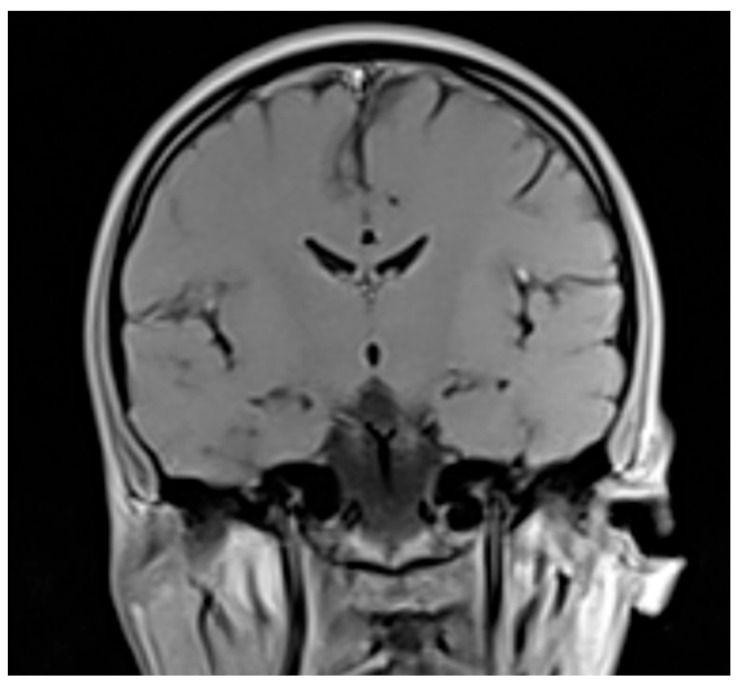

Background and Clinical Significance: Neuroleptic malignant syndrome (NMS) is a life-threatening condition usually caused by the exposure to antipsychotics. This case report presents a catatonia syndrome that may have developed in the context of a moderate NMS. Case Presentation: An 18-year-old male patient presented with a treatment-resistant catatonia syndrome that debuted 2 weeks prior to the presentation (creatin kinase levels = 4908 U/L, maximum temperature = 38.9°C, white blood count = 13.20 × 109/L, Bush-Francis Catatonia Rating Scale = 30 points). Possible organic causes of catatonia were ruled out, according to the negative results obtained. The patient's condition improved under benzodiazepine treatment and he was later discharged. After discharge, the catatonia was attributed to a possible NMS with moderate severity. The diagnosis was supported by NMS Diagnosis Criteria Score = 85 points and the presence of Levenson's triad. Conclusions: This case highlights the concomitant manifestation of both catatonia and NMS in the same patient and the difficulty of establishing a correct diagnosis involving both entities.